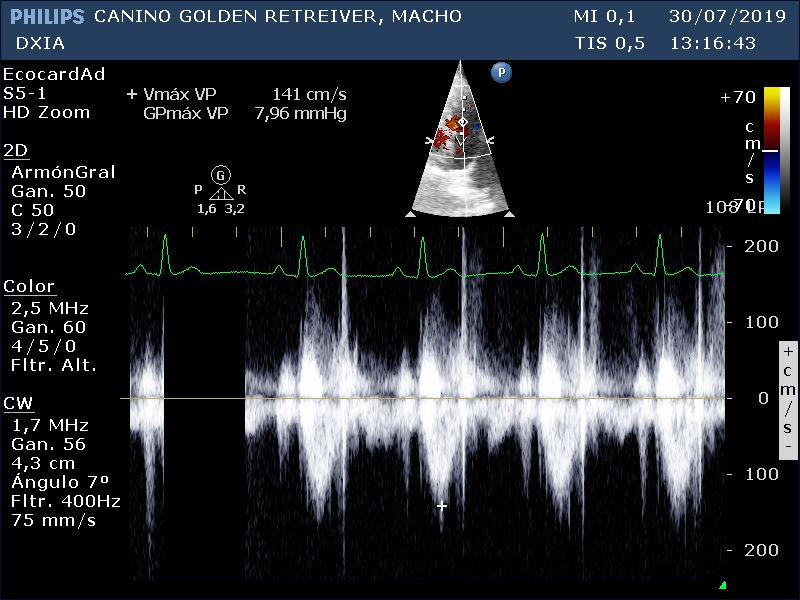

Doppler de la VP donde se observa flujo laminar con velocidad máxima de la pulmonar dentro de valores normales para la especie canina.